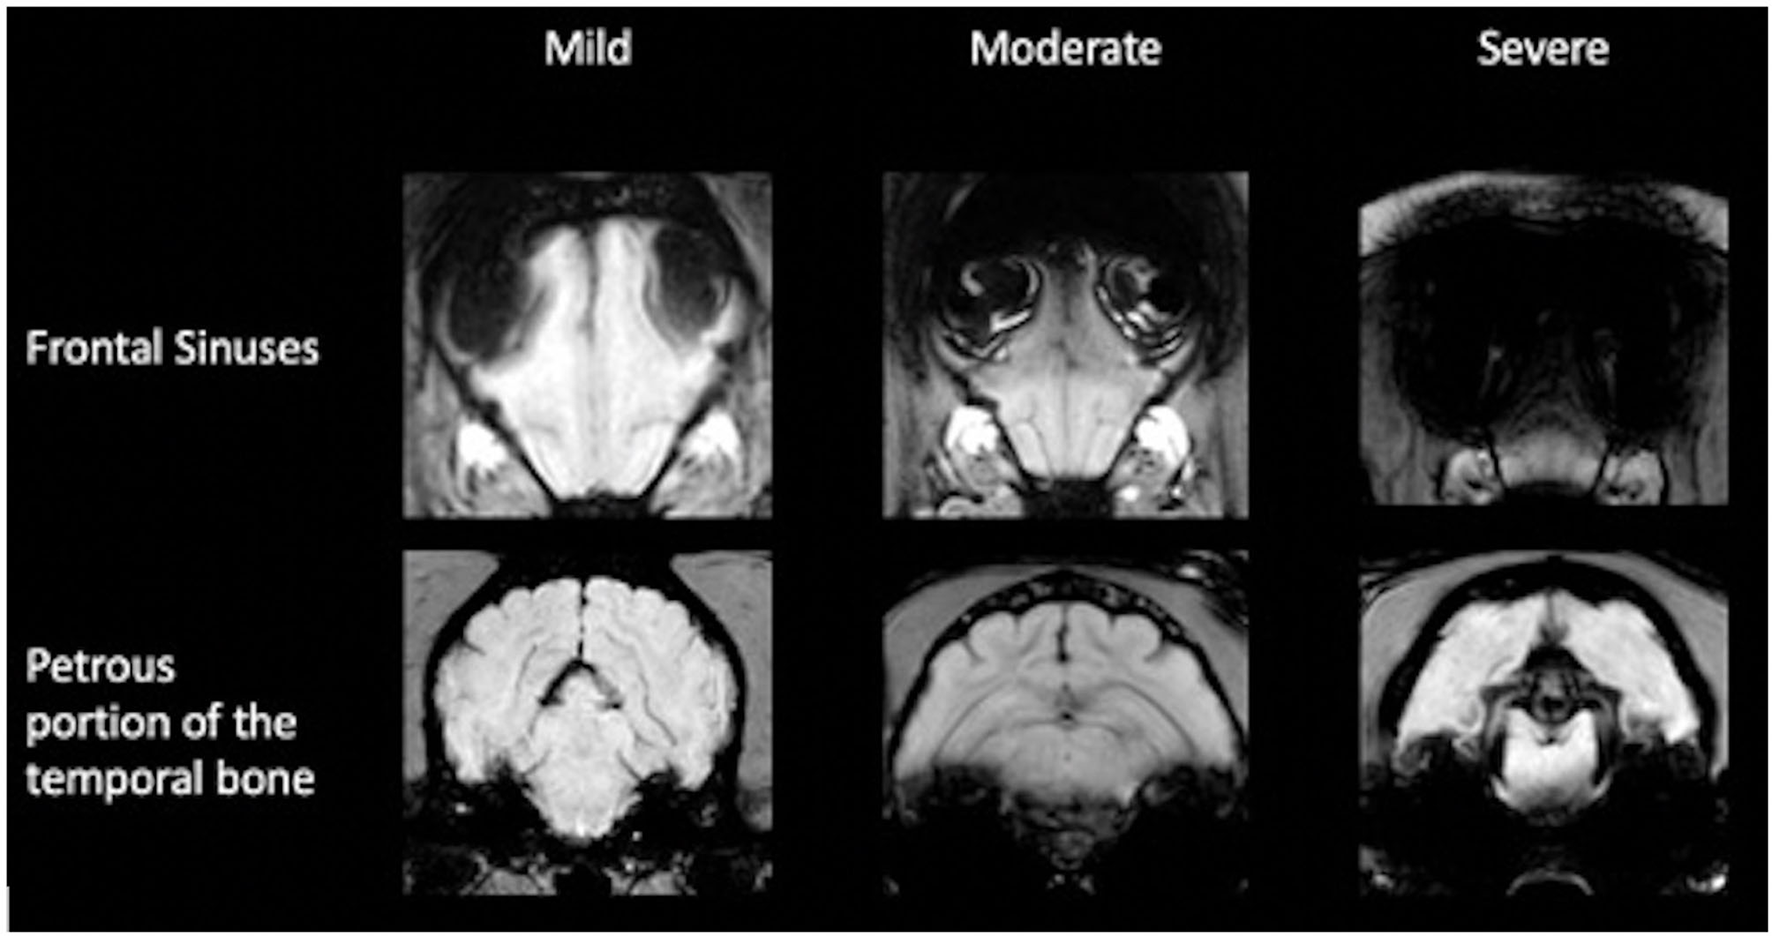

The impairment of the assessment of the sequence in the intracranial region by susceptibility artifact from the frontal sinuses and the petrosal portion of the temporal bone was subjectively evaluated. To assess the artifact, originating from the frontal sinus, the slice halfway between the most rostral portion of the brain parenchyma and the optic chiasm was subjectively graded. If the brain parenchyma at this level was affected up to one-third, it was considered as mild; over one-third to one-half as moderate; and more than one-half as. The artifacts originating from the bullae and petrosal portion of the temporal bone were assessed at the rostral aspect of the bullae. The most dorsal extent of the artifact was related to the intracranial height and classified accordingly: mild up to one-third, moderate up to one-half, and severe at more than one-half (Figure 3). Furthermore, the number of cases in which the microchip caused intracranial image distortion was recorded. Image distortion due to the microchip was not analyzed statistically because the exact localization of the microchip in relation to the vertebrae or the skull could not be evaluated in the examinations of the head.

Figure 3

Classification of image distortion at the level of the frontal sinuses and petrous portion of the temporal bone in susceptibility-weighted imaging.